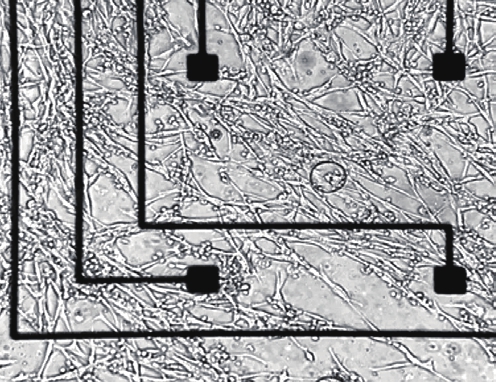

iPSCs被排列在微电极阵列(MEAs)的网格中,该阵列非常薄,可以吸附在神经末端。这产生了一层肌细胞,位于设备的电极和活体组织之间。研究人员随后将生物混合装置植入大鼠体内进行测试。他们将该设备覆盖细胞的一侧连接到大鼠前腿中被切断的尺神经和正中神经。选择这些神经是因为它们与人类上肢神经的损伤以及相关的精细运动和感觉功能的丧失相近。

与对照组相比,研究人员发现,该装置与大鼠的身体融为一体,并防止了疤痕组织的形成。此外,iPSC衍生的细胞在植入后存活了四周,这是细胞首次在这种长时间的实验中存活。

四个星期后,研究人员对植入的神经进行了测试,发现它们的行为与正常的神经一样,表明了健康的神经生理学。虽然大鼠没有恢复瘫痪肢体的运动,但该设备可以检测到大脑发送的控制运动的信号。